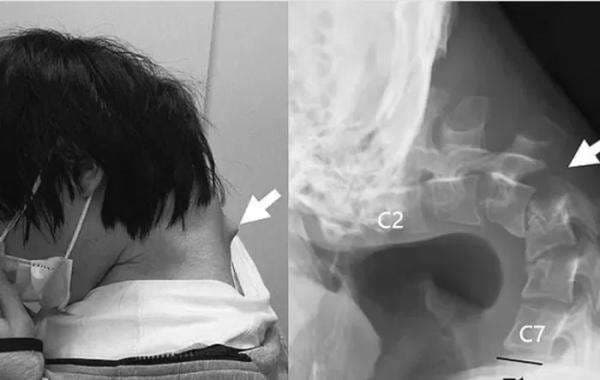

Pasien menghabiskan sebagian besar waktunya bermain ponselnya, yang menyebabkan tonjolan besar terbentuk di bagian belakang lehernya.

Ia juga tidak dapat mengangkat kepalanya menggunakan otot lehernya.

Pasien harus menjalani serangkaian operasi di mana dokter mengangkat sebagian jaringan parut di lehernya. Mereka kemudian memasukkan sekrup dan batang logam ke tulang leher pasien untuk memperbaiki posturnya.

Enam bulan setelah menjalani operasi leher, pasien akhirnya mampu mengangkat kepalanya dan mempertahankannya pada posisi yang benar.